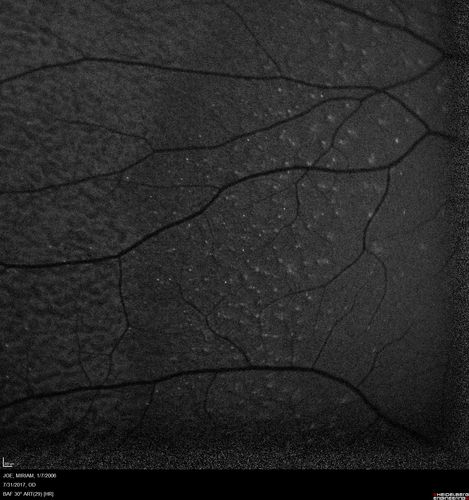

Fundus Albipunctatus

12 year old female with normal vision. She has 4 siblings all of whom have either white spots or spots on IR. Genetic testing by parents was deferred.